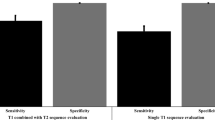

When comparing the mean ADC values of biopsy cores with or without a genetic tumor signature defined as ≥one highly significant CNA, of biopsy cores grouped according to Gleason Score or of biopsy cores with more or less than 4 highly significant mutations we found an association between lower mean ADC values and increasing tumor aggressiveness (Fig. 2).